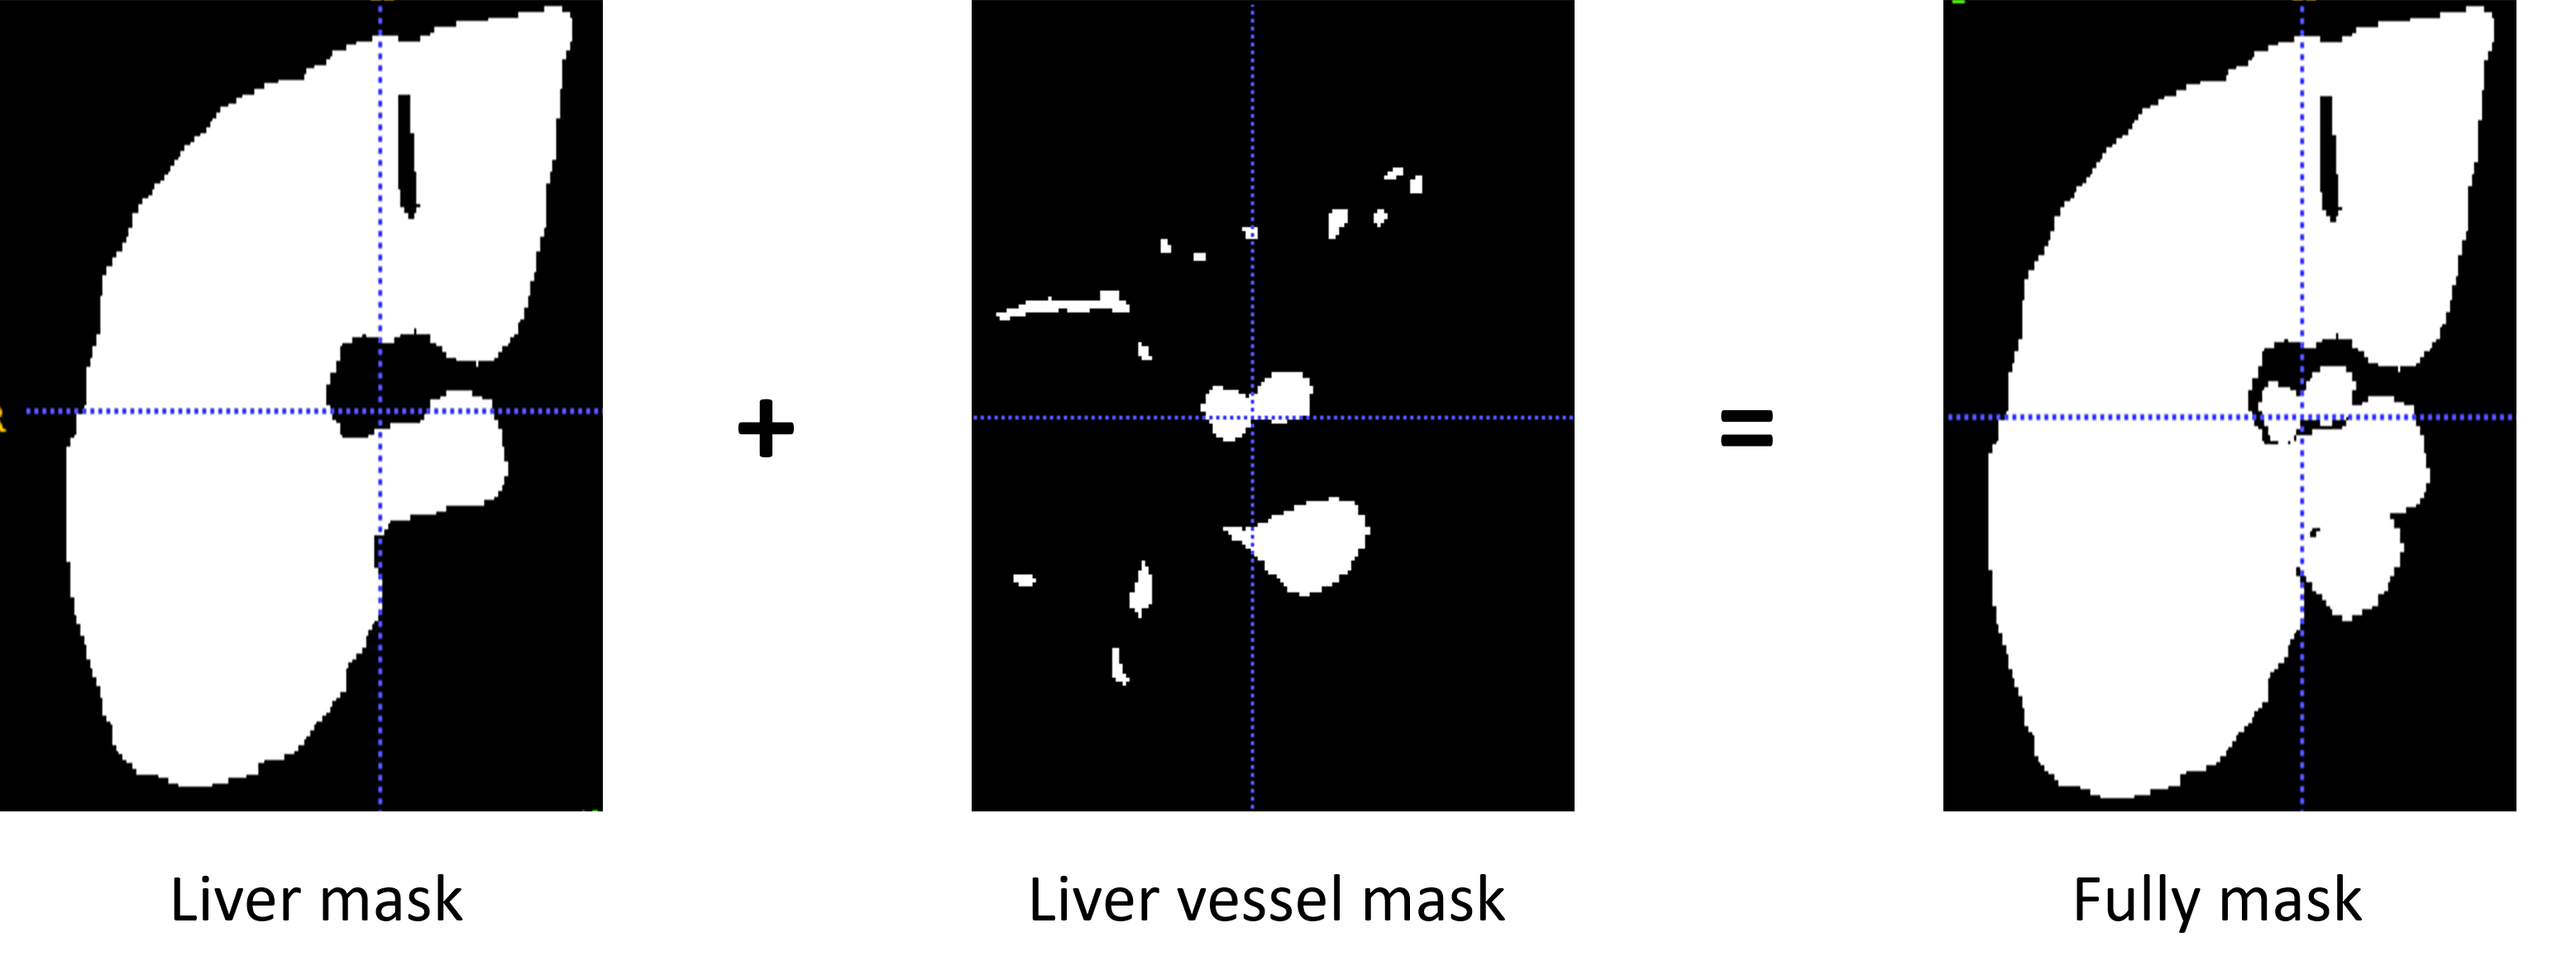

Preprocessing plays an essential role and affects the segmentation results significantlyHuang et al. (2018); Isensee et al. (2018). For example, applying preprocessing to lower the background noises and augment image contrast. Therefore, we arranges preprocessing as 4 steps: (1)3D IRCADb provides 20 groups of CT images, liver vessel masks and liver masks. We crop CT images and liver vessel masks to liver region boundary as the ROI. Then adjust to the size to 256x256x192 to unify the model input. (2)We truncate the intensity of all voxels in the volumes to the range of [-50, 250] HU to reduce the irrelevant details and increase image contrast. (3)In order to remain enough vessels’ continuity features, we add vessel mask outside the liver as supplement of vessel information(Eg.Fig.1). (4)Images are normalized to zero mean and unit variance. Because most liver vessels are quite small, we keep images with their original resolution can prevent artifact errors caused by resampling.

Refer to caption

Figure 1: supplement of vessel mask used in the training set